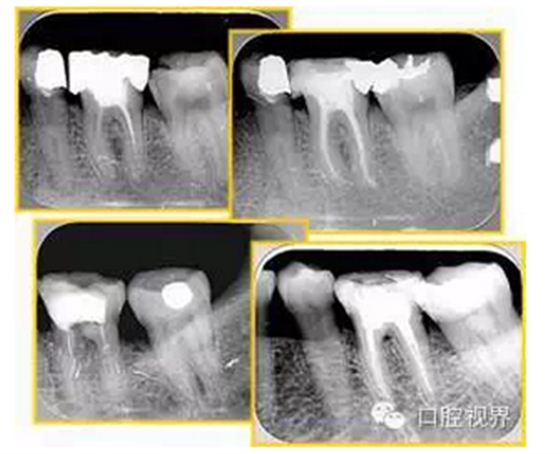

6. 術(shù)后 X 線片

術(shù)后 X 線片用來評定根管充填 長度、致密度(管壁清晰、側(cè)枝)等指標(biāo)。

左圖為根管充填術(shù)后 X 線片。圖中可見,根管充填較好。右下圖有白色小點(diǎn),為側(cè)方加壓導(dǎo)致糊劑擠出所致,表明根管充填比較致密。

致密、恰到好處的充填可去除干凈根管里感染灶,機(jī)體逐漸恢復(fù)。

多根牙時(shí)候需進(jìn)行偏移投照,正位投照無法說明具體哪根牙根管充填效果。